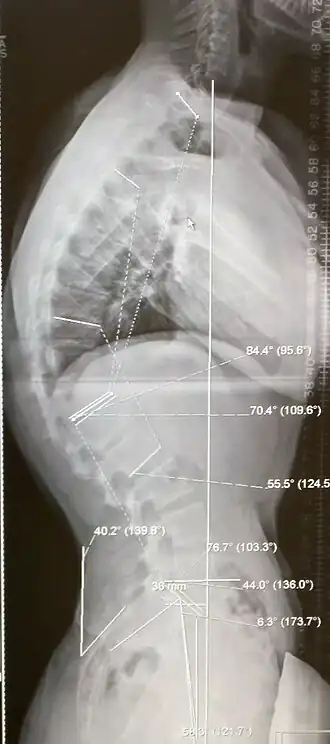

Radiographie

Le diagnostic repose sur des clichés simples du rachis de profil. Le rachis dorsal doit être exploré par un cliché de profil réalisé debout.

En cas de forme symptomatique, le cliché simple de rachis dorsal de profil doit être complété par deux clichés de rachis dans son ensemble pour analyser la statique.

Sur le plan radiologique la cyphose est en général supérieure à 50°.

- d'un cliché de profil de l'ensemble du rachis en position debout ;

- d'un cliché de profil du rachis dorsal centré sur D4-D8 ;

- d'un cliché de face du rachis pour rechercher une éventuelle scoliose associée.

- prédominance des lésions entre les vertèbres D4 et D8 ;

- cyphose à grand rayon ;

- aspect cunéiforme (déformation en coin du corps vertébral) des vertèbres situées au sommet de la cyphose ;

- plateaux vertébraux irréguliers et feuilletés ;

- possibles hernies intra-spongieuses ou rétro-marginales antérieures :

- possible tassement discal.

Le diagnostic de la forme classique est porté devant la mise en évidence radiologique d'une cunéiformisation de 5 degrés ou plus d'au moins trois vertèbres adjacentes situées à l'apex de la cyphose.